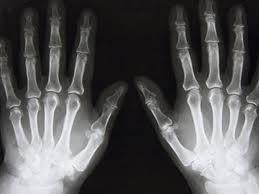

Современный рентгенологический кабинет торжественно открыли в 9-ой городской больнице в Балаклаве в четверг, 8 ноября.

«Новое оборудование соответствует современным стандартам в медицине и сможет обеспечить диагностикой не только жителей Балаклавы, но и близлежащих сел» – отмечает главный врач городской больницы №9."

Новое оборудование поступило в Балаклавскую больницу.